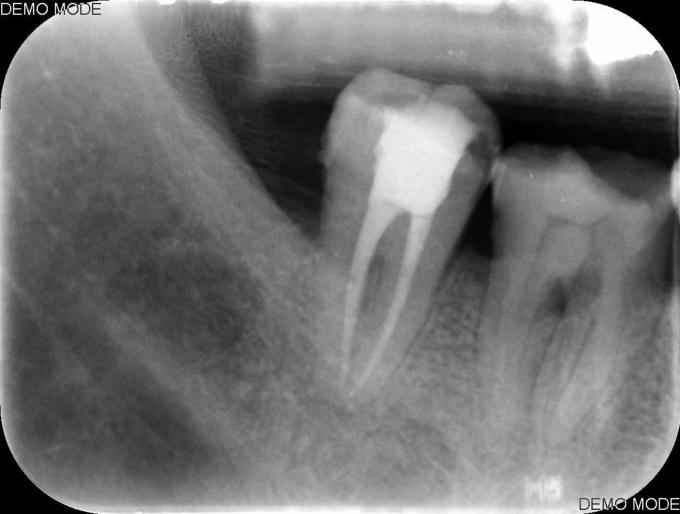

诊断:牙髓坏死 治疗#47碧兰麻下开髓,封三甲+OC球,ZOE暂封,嘱2周后复诊,不适随诊。 去暂封,清理髓腔及根管,双氧水和生理盐水交替冲洗,测WL,拍片试尖达工作长度,根管内导入糊剂,侧压充填中下段,热牙胶充填上段,X线示恰填,树脂充填修复。